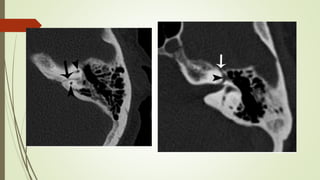

Evaluación Imagenologica

• #38 Izqu. AXIAL-- fxLongitudinal perdonan la capsula otica (laberinto oseo) Centro AXIAL fx trnasversa lascuales tperdonan el lab erinto oseo Dere: MIXTA – tmp perdona